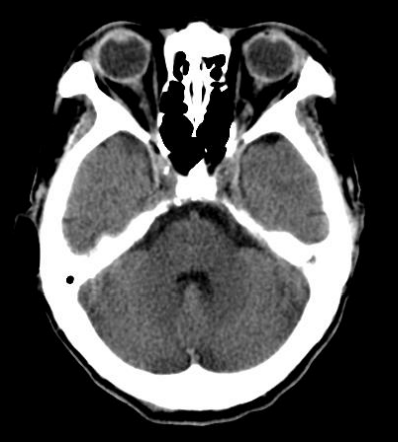

A tomografia computadorizada das órbitas é um exame de diagnóstico por imagem de alta qualidade, que permite a avaliação desta região de maneira anatômica, sendo ela um exame que serve não só para auxiliar o médico no estudo de diversas patologias (doenças) como também para avaliar as respostas aos tratamentos. Em algumas situações, é solicitado o uso de contraste iodado – via endovenosa –, para uma visualização mais detalhada da área desejada.

A órbita é uma cavidade do esqueleto da face onde se “encaixa o olho”. Anatomicamente tem uma forma de pirâmide, permitindo acomodar o bulbo do olho, os músculos que permitem a movimentação do olho, os nervos, os vasos sanguíneos e o aparelho lacrimal (para a produção de lágrimas).